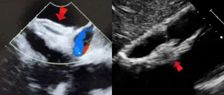

宋光远-经导管MVIV手术演示